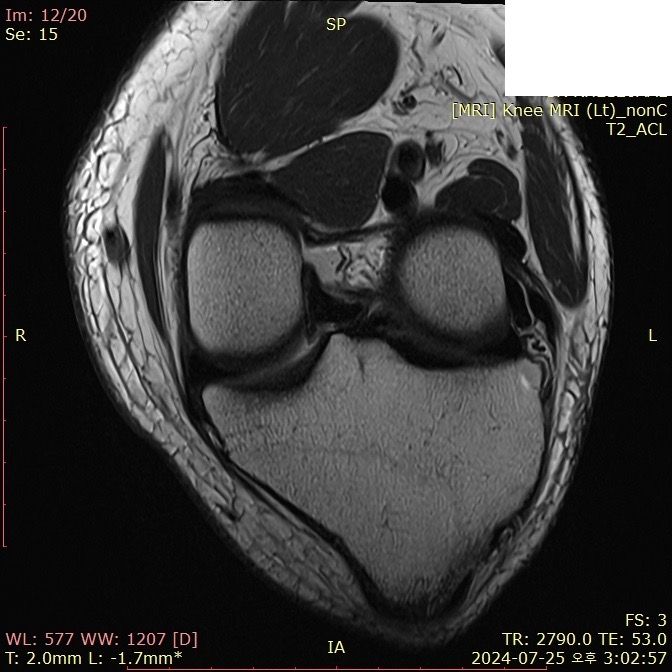

무릎 ACL(전방십자인대) 확인 부탁드려요

아스팔트에 무릎을 부딪쳐 심하게 부어서 mri 찍어봤는데 슬개골 비변위성 골절 판독 받은 건 기억 나는데, 인대는 기억이 잘 안나서 여쭤 봅니다..

전방십자인대 괜찮은가요...??ㅠㅠ